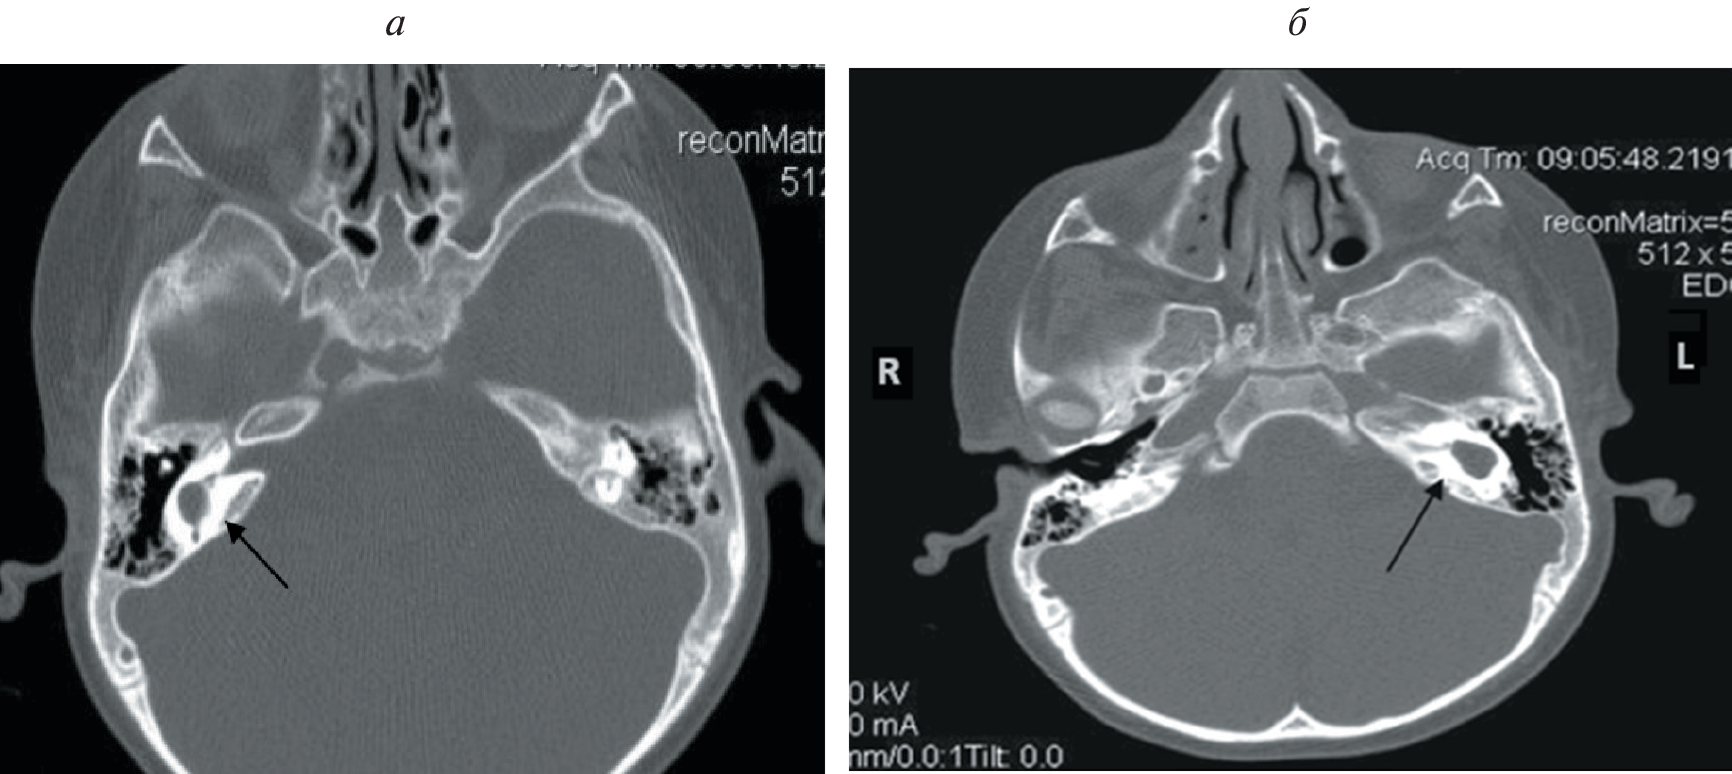

По данным различных авторов, у 20% детей с сенсоневральной тугоухостью или глухотой по результатам компьютерной томографии определяются аномалии строения височных костей. Кохлеарная имплантация при наличии кохлеовестибулярных аномалий сопряжена с рядом трудностей. К ним относятся особенности выполнения кохлеостомии и размещения электрода внутри улитки, риск повреждения лицевого нерва из-за его аномального расположения и его аберрантная стимуляция в послеоперационном периоде, интраоперационная ликворея, что может привести к развитию бактериального менингита в послеоперационном периоде, а также опасность проникновения электрода во внутренний слуховой проход. В данной работе представлен наш способ выполнения кохлеарной имплантации при аномалии развития внутреннего уха – общей полости. Способ расширяет возможности кохлеарной имплантации для восстановления слухового восприятия у пациентов с данной патологией.